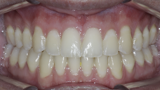

New Age orthodontics and orthopaedics with temporary anchorage devices